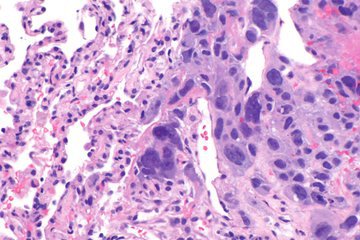

Доктор Антон Елкин заявил, что в большинстве своем папилломы не несут большой опасности, однако в некоторых случаях лучше проконсультироваться с врачом, поскольку они могут переродиться в рак.